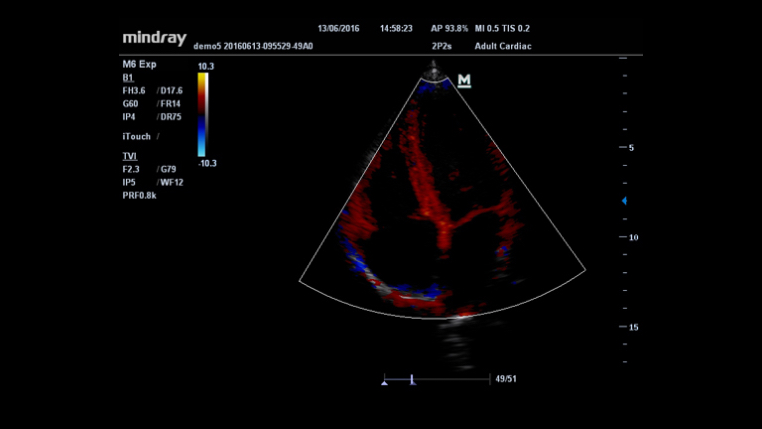

An innovative technology to better visualize tiny vessels and complex flow patterns, based on Mindray's exclusive processing algorithm.

iTouch? (Auto Image Optimization)

Gain instant auto image optimization in B, Color and PW Modes on the click of single key.